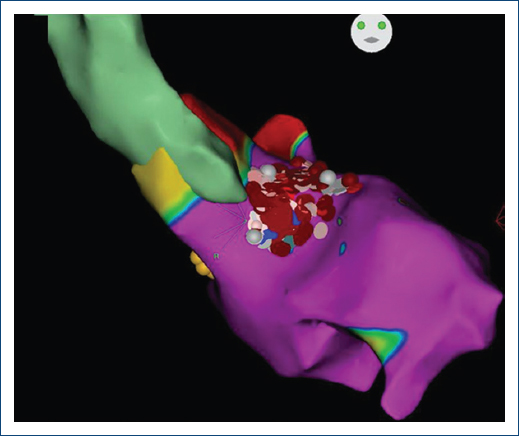

Figure 1 3D guided anatomical map of the left ventricle and radiofrequency ablation lesions (gray and red dots) His bundle in yellow dots. Anteroposterior view.

A 21-year-old female who was diagnosed at 10 years old with HOCM underwent ERASH treatment. The clinical examination revealed a systolic 3/6 murmur in the third left intercostal space and signs of left ventricular hypertrophy on the electrocardiogram. Transthoracic echocardiography showed an ejection fraction (EF) of 61%, with LVOT peak gradients of 93 mmHg at rest and 122 mmHg during the Valsalva maneuver. TTE also indicated severe posterior wall/septum thickness (17/30 mm), septal, anterior movement (SAM) with moderate mitral regurgitation, and papillary muscle displacement. Cardiac magnetic resonance imaging revealed an EF of 72% and significant late gadolinium enhancement in the basal inferoseptal, mid anteroseptal, mid inferoseptal, mid inferior, and apical inferior left ventricle (LV) segments, comprising 29% of the myocardial mass, which is why a dual-chamber Medtronic ICD implanted for primary prevention. The patient underwent an ERASH procedure guided by intracardiac echocardiography (ICE) and 3-D electroanatomic mapping – the ERASH procedure performed under general anesthesia – ICE used for real-time visualization and guidance. Access to the LV septum was retrograde. Electroanatomic mapping (CARTO, Biosense Webster) was integrated with ICE to accurately localize the ablation targets and tag his bundle to prevent further injuries (Fig. 1). Ablation was performed using an irrigated RF catheter (Thermo-cool, Biosense Webster). Each session was done at 50 W for 30 s, with a force of 10-40 g/lesion. Ablation targeted the obstructive part of the septum to reduce the LVOT gradient. Initial LV hemodynamics revealed 125/20 mmHg, with an LVOT gradient of 100 mmHg preoperatively. The patient's final gradient was 76 mmHg at the end of the RF ablations. A surgical exploration needed to be done once the procedure finished due to persistent pericardial effusion. Surgical findings showed a right ventricular lesson, likely associated with the ICE catheter and not for the RF points since this procedure was done in a different localization than the perforation showed. No perforation of the LV was observed during the surgical revision.